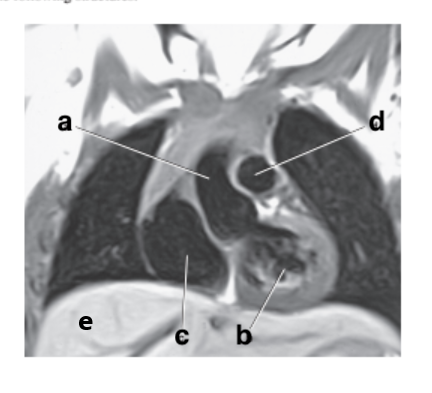

What is letter b ?

Esophagus

Which letter is the Pulmonary trunk ?

d

Which letter is the Descending aorta ?

f

Left ventricle

Which letter is the superior vena cava ?

Left atrium